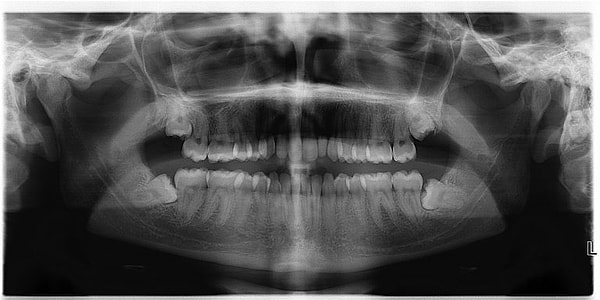

4. Зубы мудрости

Эти зубы раньше использовались, чтобы измельчать пищу, но сейчас для этого у нас есть вилки и ножи. У большинства людей вообще зубы мудрости не вырастают.